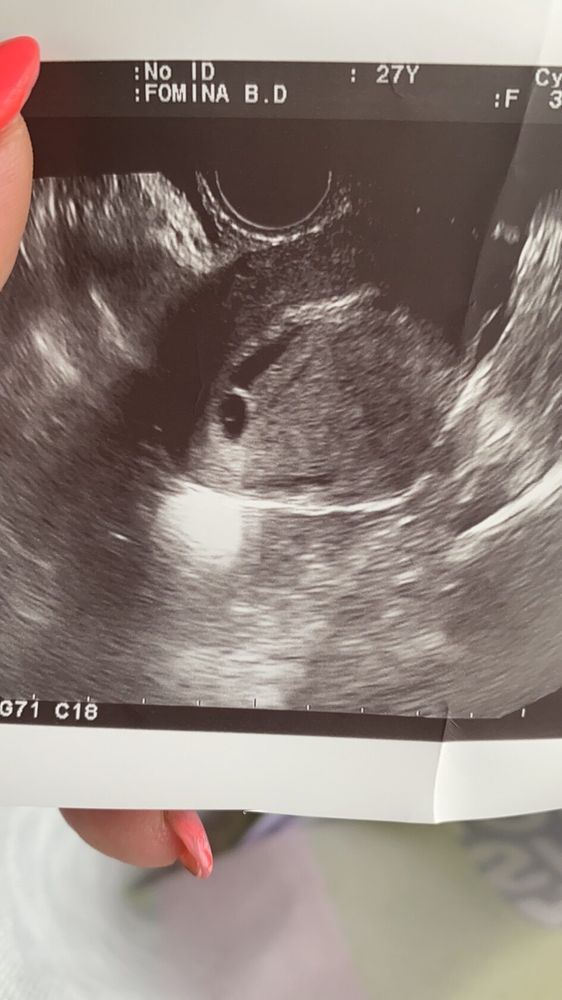

25 дпо узи

Сходила сегодня на узи, завтра ложусь в больницу((( Огромная гематома . Моя гинеколог говорит, что такое чувство что хотели начаться месячные , началась отслойка ( когда кровило на 12 и 13 дпо) , но мы их остановили . Так что я всегда за то, чтобы все-таки делать тесты до задержки , вот если бы я не узнала, что беременность есть, то просто бы подумала,что начались месячные . Без дюфа говорит мне тоже никак.

вот сдесь на фото сверху видно мою огромню гематому и справа снизу плодное яйцо